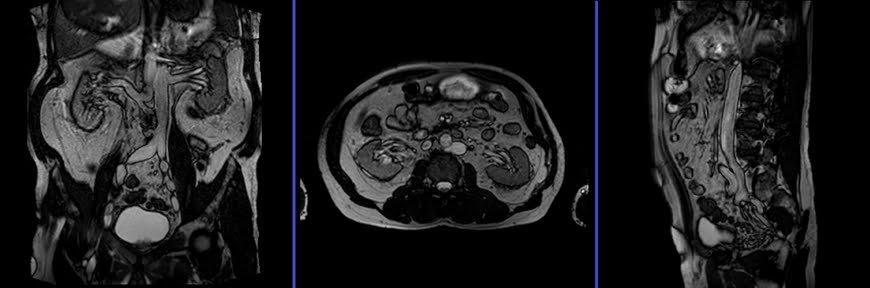

MRI Kidney Ureters and Bladder (KUB) Localizer

A three-plane T2 TRIFISP\HASTE localizer must be taken initially to localize and plan the sequences. These are fast single-shot localizers with under 25s acquisition time, which are excellent for localizing vascular structures. Take at least 5-8 slices in all planes to get the best results.